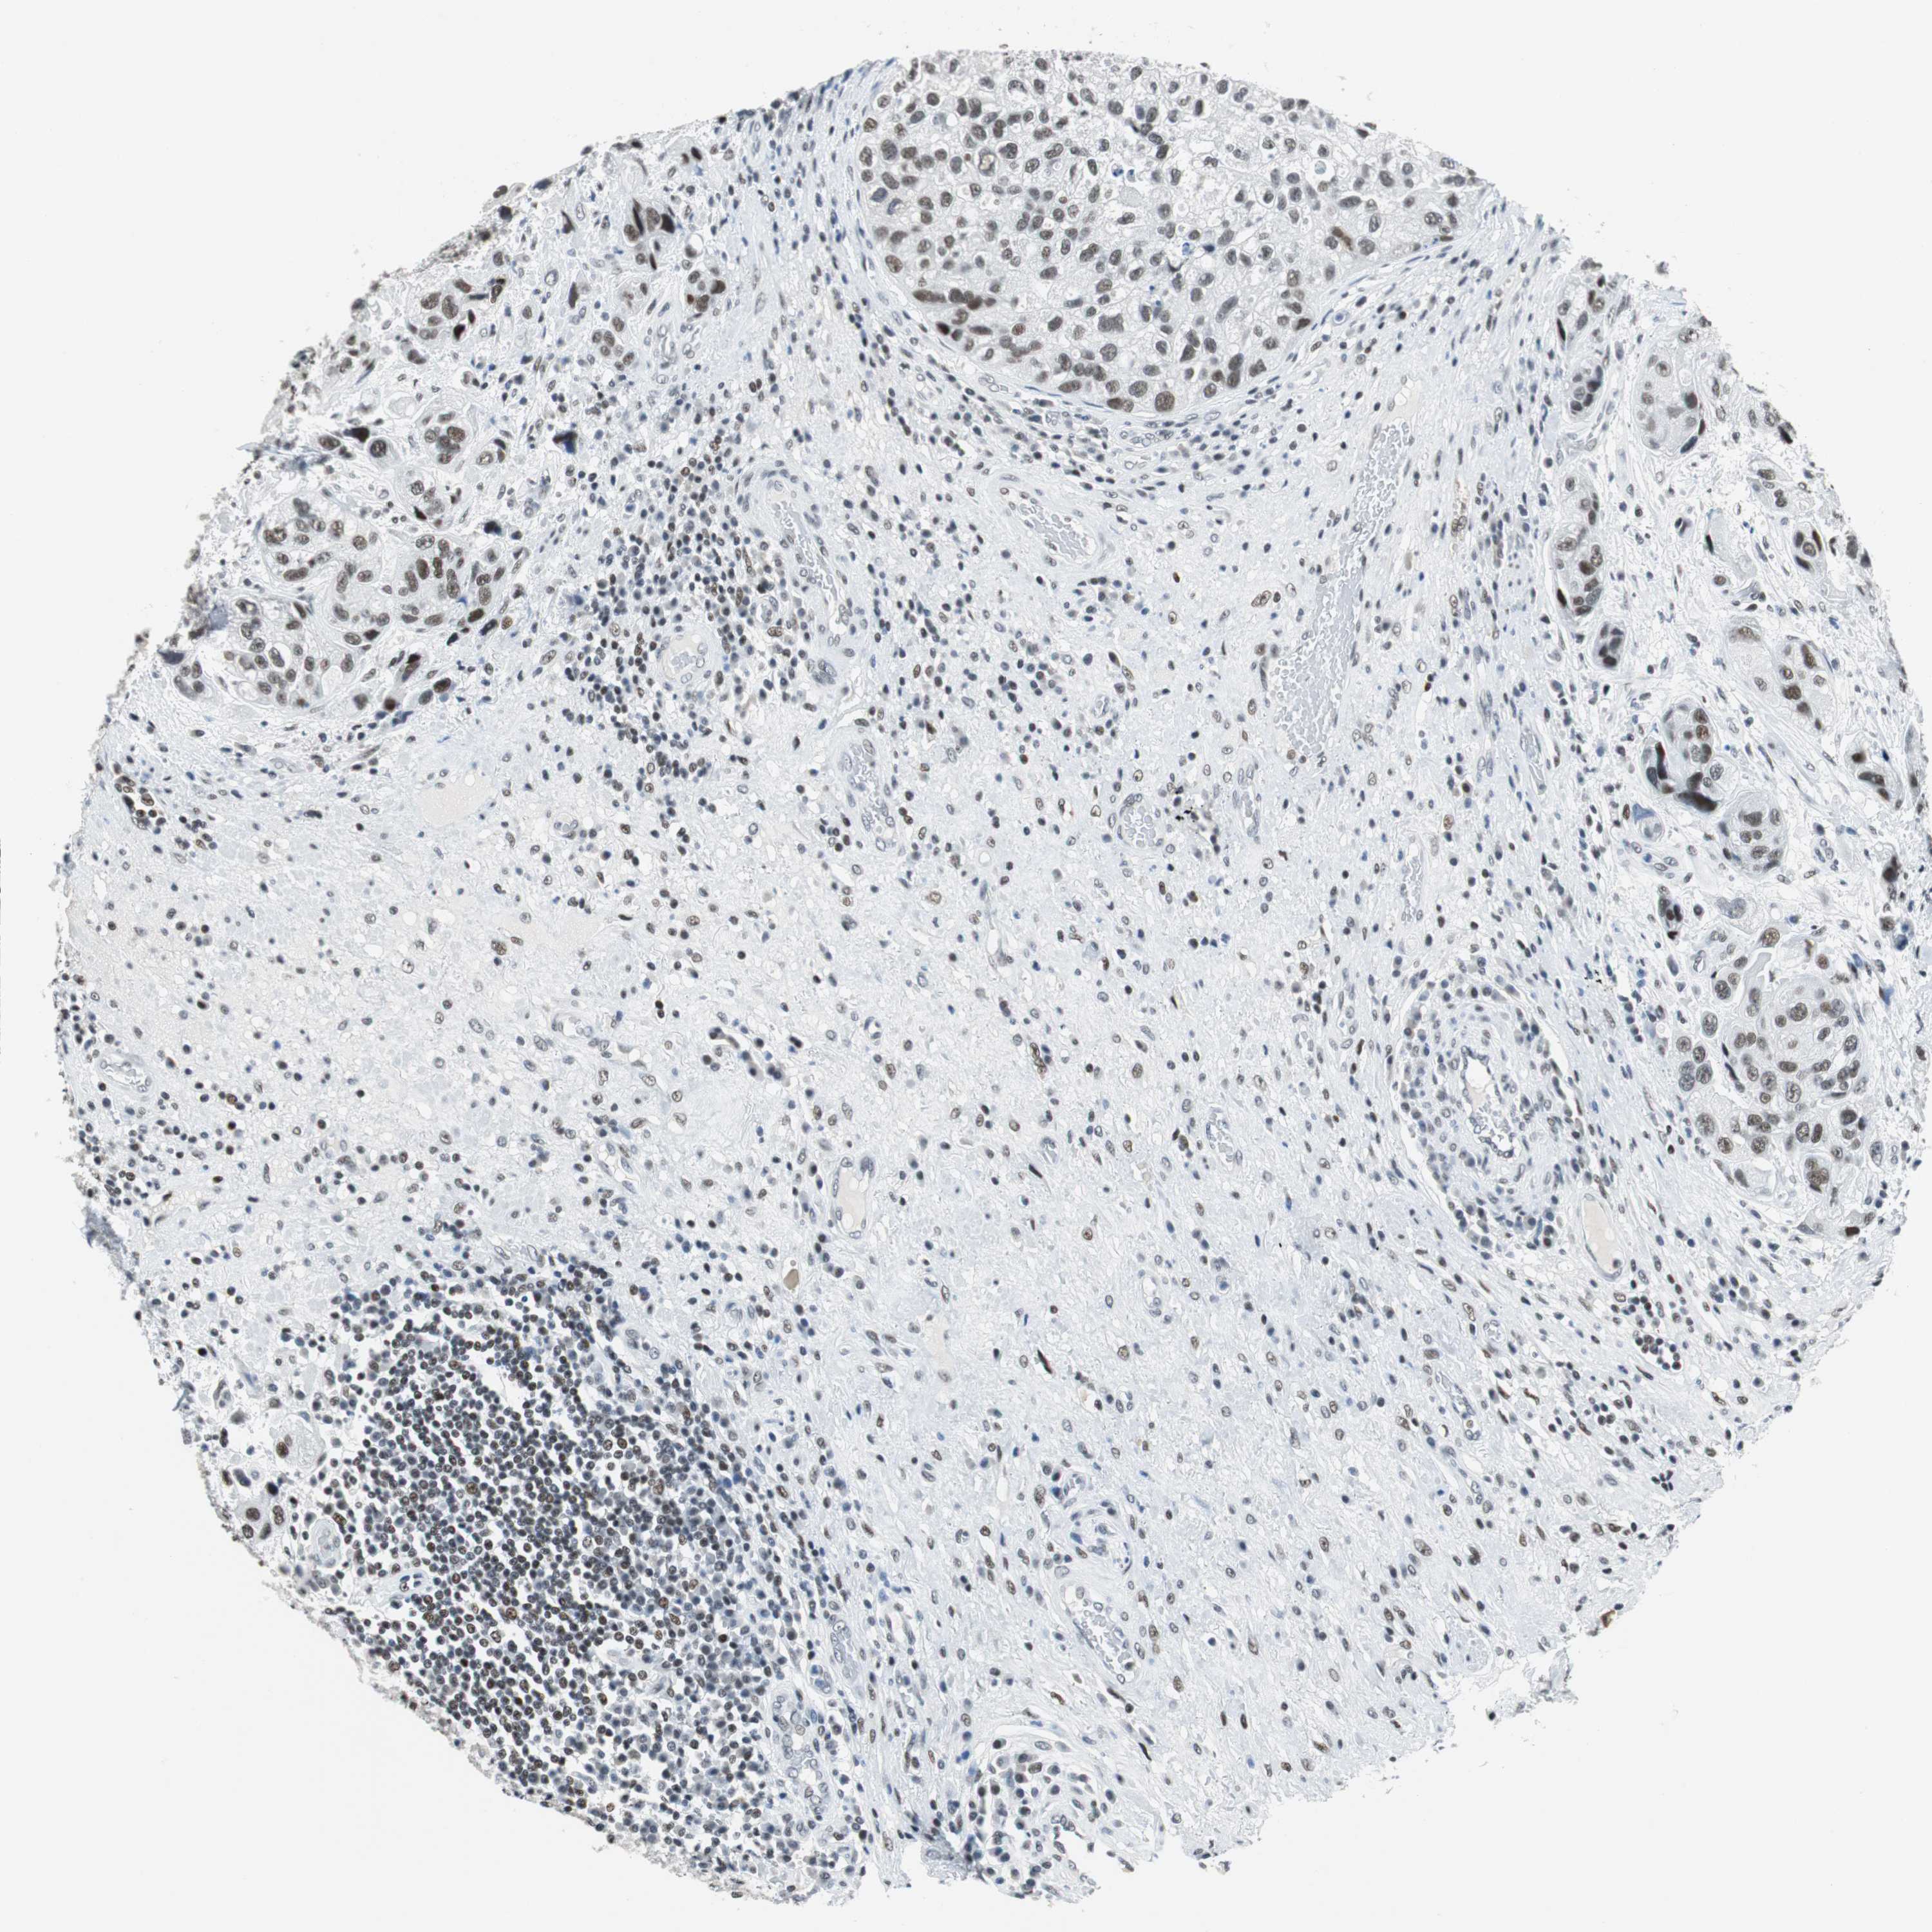

UROTHELIAL CANCER - Protein expressioni

A mouse-over function shows sample information and annotation data. Click on an image to view it in a full screen mode. Samples can be filtered based on level of antibody staining by selecting one or several of the following categories: high, medium, low and not detected. The assay and annotation is described here.

Antibody stainingi

Antibody staining in the annotated cell types in the current human tissue is reported as not detected, low, medium, or high, based on conventional immunohistochemistry profiling in selected tissues. This score is based on the combination of the staining intensity and fraction of stained cells.

Each image is clickable and will lead to virtual microscopy that enables deeper exploration of all samples and also displays staining intensity scores, fraction scores and subcellular localization as well as patient and tissue information for each sample.

Antibody HPA052052

Antibody CAB005583

Antibody CAB072336

Staining

High

Medium

Low

Not detected

Intensity

Strong

Moderate

Weak

Negative

Quantity

>75%

75%-25%

<25%

None

Location

Nuclear

Cytoplasmic/membranous

Cytoplasmic/membranous,nuclear

Urothelial carcinoma, High grade

Urothelial carcinoma, Low grade

Urothelial carcinoma, NOS